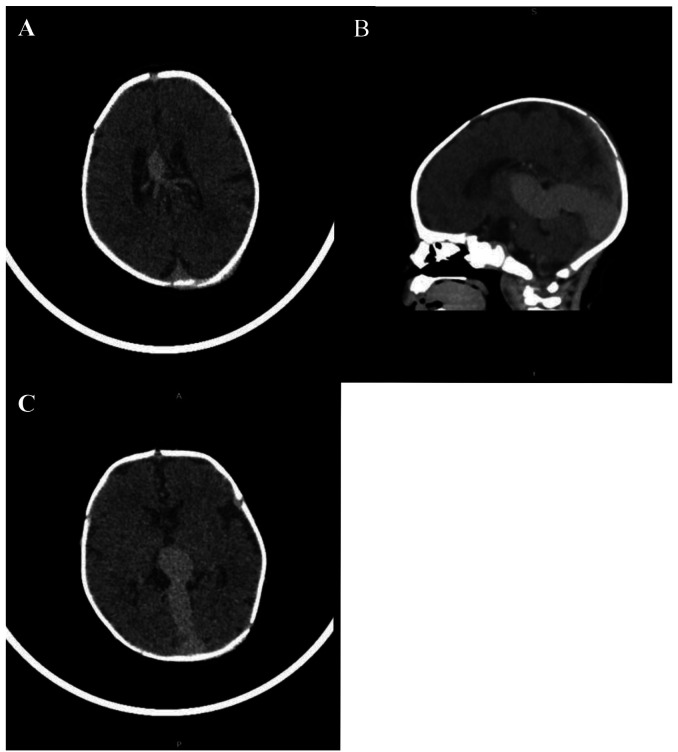

In this article, we present a neonate with the vein of Galen aneurysmal malformation, a rare blood vessel malformation of the brain, which was clinically manifested by signs of cardiac failure. Cranial ultrasound suspected the existence of the vein of Galen aneurysmal malformation, and the diagnosis was confirmed by computed tomography and magnetic resonance imaging. Based on our case, we believe that cranial ultrasound should be included in the screening protocol for neonates with cardiac failure. In addition, we believe that endovascular embolization of the blood vessels that supply the aneurysm is the method of choice in treating the vein of Galen aneurysmal malformation. Treatment of neonates with the vein of Galen aneurysmal malformation is challenging and requires a multidisciplinary approach (neonatologists, cardiologists, neuroradiologists, and neurosurgeons).